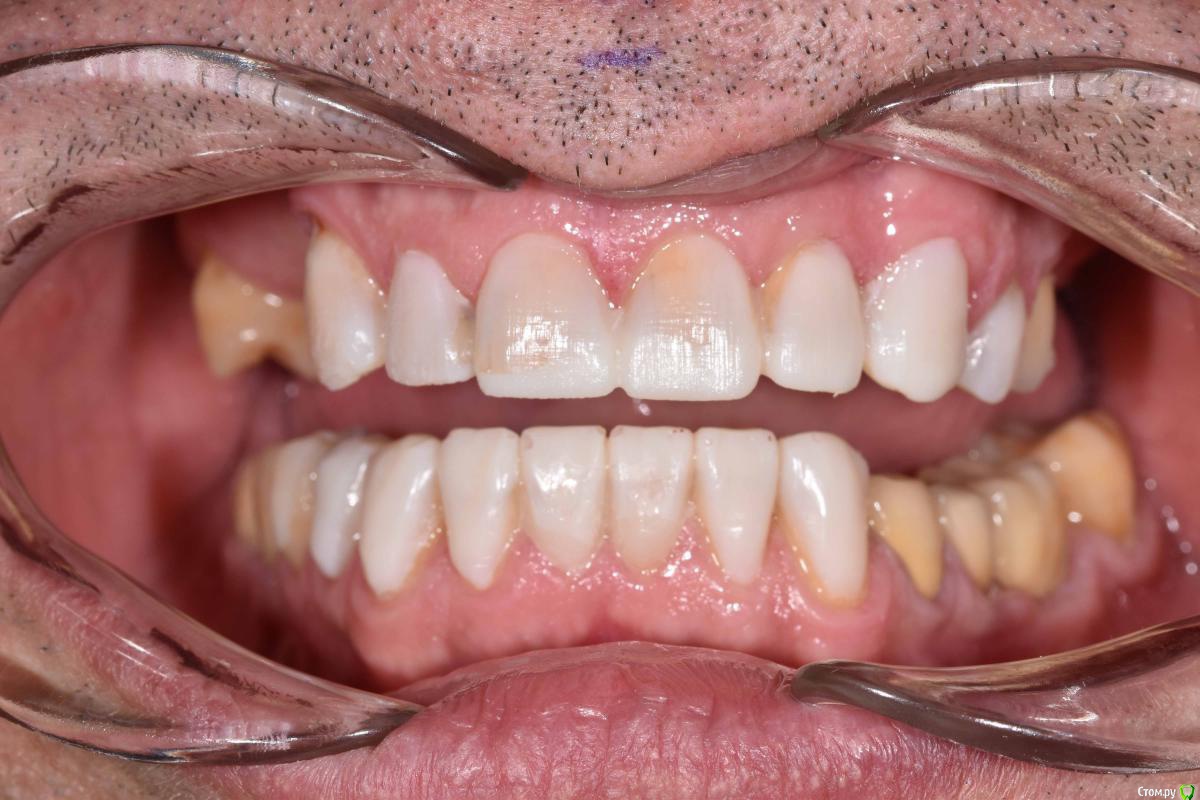

Neilrus Опубликовано 24 января, 2019 Поделиться Опубликовано 24 января, 2019 Здравствуйте, коллеги. Вопрос по выбору типа реставрации, есть пациент с полностью несъемным низом, а вот на верхней челюсти посмотрите на фото и снимок, пожалуйста, 17зуб, потом 13-25. Имлантация на верхней челюсти в ближайшие годы не предвидится по ряду причин. отработали пациента на капах, утвердили мокап, скоро начнем. Стираемость изнутри восстановлю композитом и обработаю под коронки. Вопрос по типу коронок, хочется и красиво и надежно.Верх: Понятно что если иметь ввиду что это мужик с такой объемной потерей тканей, да еще со съемником, то центр желательно цирконий, может даже преттау, но адгезия плохая пугает, да и внешний вид даже с хорошим техником не очень.Дисиликат с нанесением? Как вы считаете, выдержит?Гипертонуса нет, не бруксист, будет каппа ночная на низ, конечно Низ: Тут выбор между коронками и винирами (не на огнеупоре ,а обычные)жевательные низ пока временные, потом выведу их по плоскости, там emax без нанесения будут и цирконий на импл. Как бы поступили вы? Ссылка на комментарий